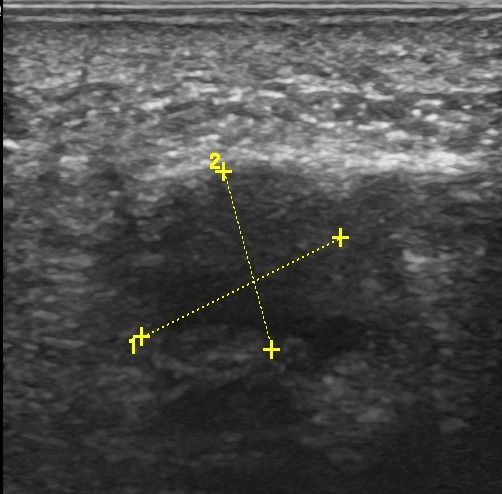

Foot Nerves

- Morton's Neuroma